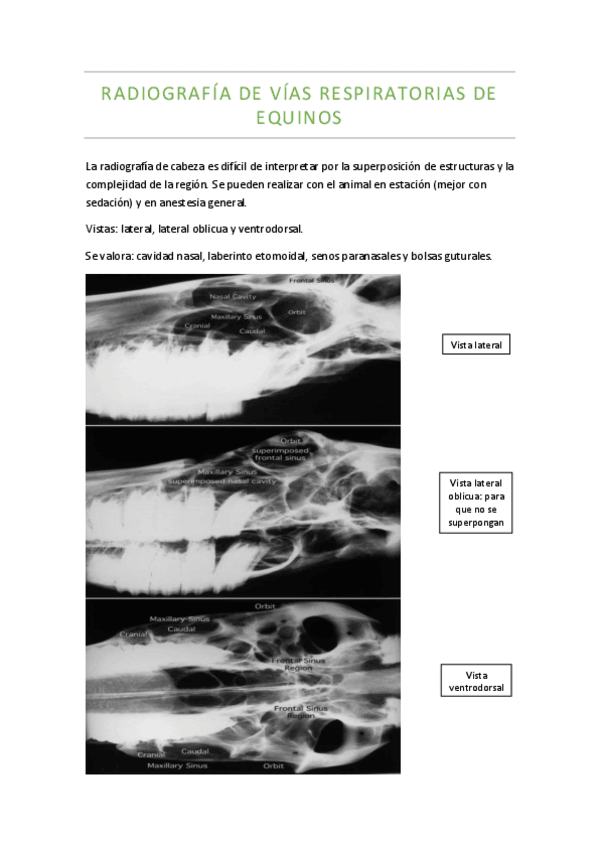

Radiografia-de-vias-respiratorias-de-equinos.pdf